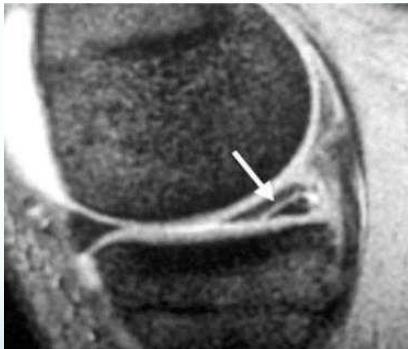

Diagnostic Studies

MRI

Meniscal Repair

- Indications: Peripheral, longitudinal tears in red zone (due to blood supply)